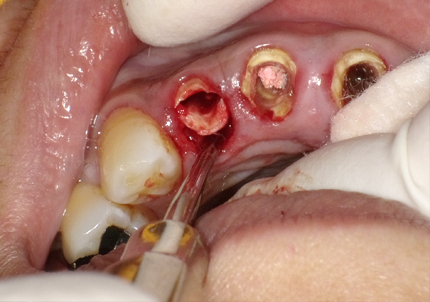

4.右上2番 S.S.T(ソケットシールドテクニック)

5.左上1番 S.S.T(ソケットシールドテクニック)

6.左上2番 S.S.T(ソケットシールドテクニック)